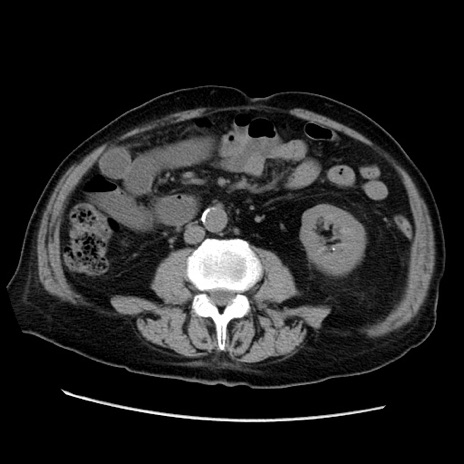

症例21(横断像)

【症例】70歳代男性

【主訴】腹痛

【現病歴】肝硬変・肝細胞癌にてかかりつけの方。約9時間前に食後より腹痛出現。症状が徐々に増悪し、嘔吐出現したため来院。

【既往歴】肝硬変、肝細胞癌(RFA、TACE後)

【身体所見】意識清明、表情苦悶様、BT 36℃、BP 129/78mmHg、P 88bpm、SpO2 97%(RA)、右上腹部から心窩部にかけて圧痛あり、反跳痛なし、筋性防御あり。

【データ】WBC 5800、CRP 0.16